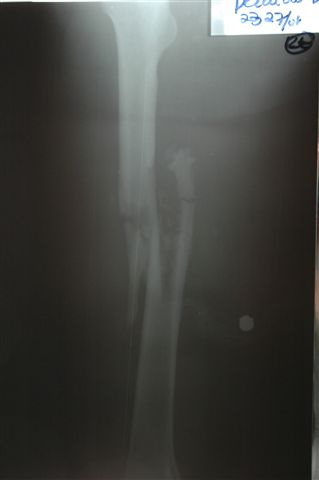

В приложении пример огнестрельного ранения бедра, оперированного на 2 сутки после ранения. Штифтование было выполнено только на вторые сутки по причине задержки перевода из другого госпиталя, АБ профилактика была начата в другом учреждении, с момента госпитализации пациента к ним. Входное пулевое отверстие и зона введения штифта зажили первичным натяжением.

Единственно что наблюдал - замедленная консолидация, судя по серийным Рг граммам. В приведенном случае прии вялом мозолееобразовании сделал ошибку, решившись динамизировать гвоздь - перелом сросся со значительным укорочением бедра - повторная хирургия по удлинению бедра и проксимальным запиранием, больной мобилизован и вполне доволен(кстати заметить больной с ВИЧ инфекцией - изначально скомпрометированный иммунитет и несмотря на это, всё прошло без костной и мягкотканной инфекции.